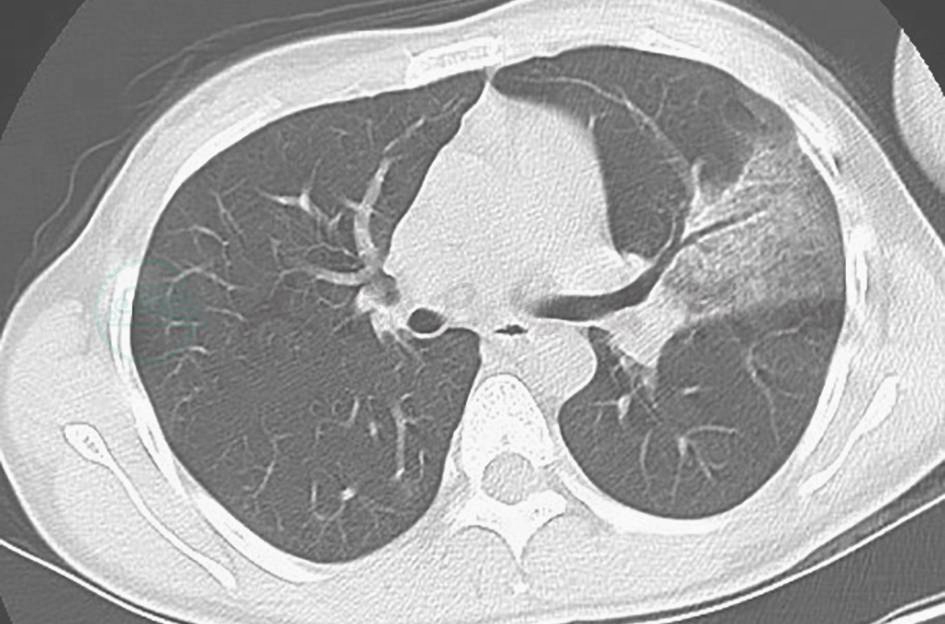

特殊感染:本例患者外观消瘦,双肺多发病变,抗感染治疗后病情反复,须注意排除肺结核,尤其肺结核所致干酪性肺炎(图3、图4)。肺结核的胸部影像学表现可为实变,密度多不均匀(中心密度高,边缘模糊),其中可有多个融合区,好发于上叶尖后段和下叶背段,病变肺段体积缩小,胸廓塌陷,大多数同时可见空洞、钙化、卫星灶等,由于沿支气管传播,病变多在相邻的多叶段内。本例患者的胸部影像学表现与此不符,可进一步查PPD、T-SPOT检测、痰抗酸染色等以排除该病。

图4 干酪性肺炎胸部影像学表现

胸部CT可见双中下肺可见较弥漫斑片状高密度影,病灶沿支气管分布,并见树芽征